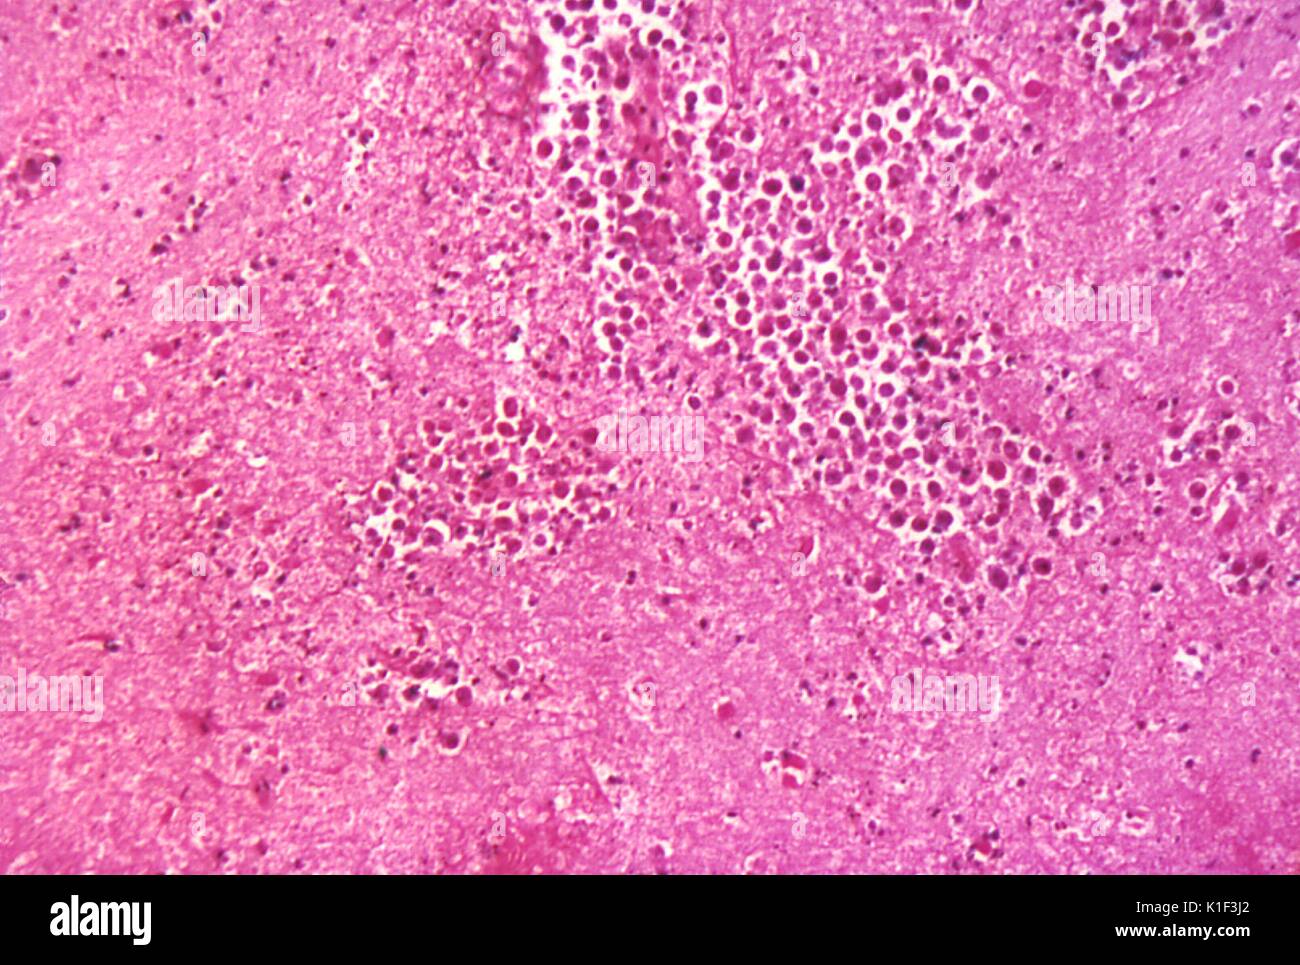

L'ameba segue le fibre nervose olfattive, dalla regione olfattiva migra successivamente ad altre aree del cervello, dove si nutre del tessuto nervoso, con conseguente necrosi e sanguinamento significativi. Il parassita comincia quindi a consumare le cellule del cervello mediante un amoebostomo, un apparato di aspirazione ricco di actina che si estende dalla sua superficie cellulare Tutto ciò provoca il quadro di meningoencefalite amoebica primaria (PAM o PAME).